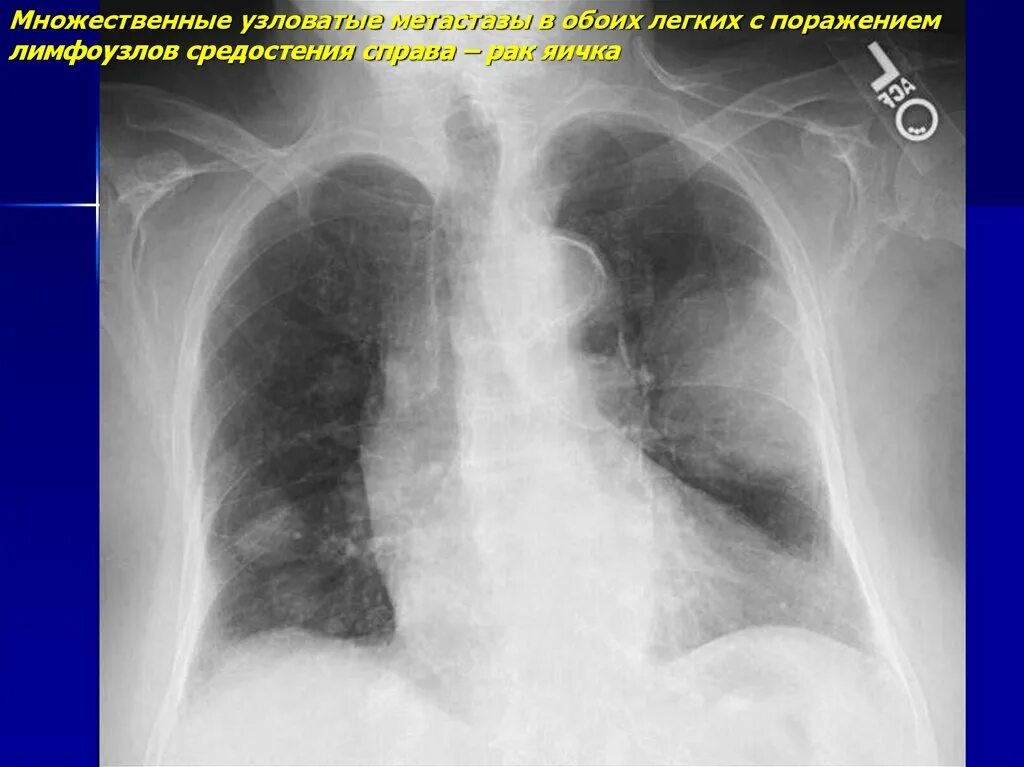

Метастазы в средостении легких